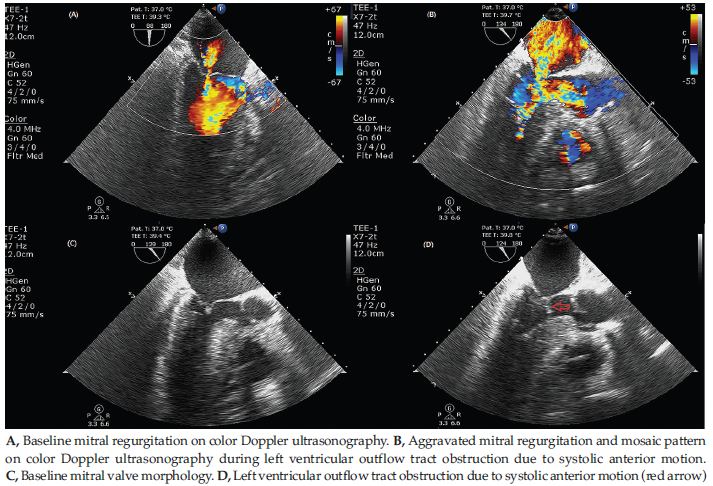

Intraoperative TEE revealed severe central mitral regurgitation and LVOT mosaic flow pattern not seen on baseline examination (Figure 3). For suspected LVOT obstruction, inspired oxygen was increased to 100%, and vasopressor infusion (norepinephrine 0.2 µg/kg/min, vasopressin 0.05 U/min, terlipressin 2 µg/kg/h) and volume management were initiated. Bolus doses of phenylephrine (100 µg and 200 µg), norepinephrine (10 µg), and vasopressin (1 U) were given. Due to persistent instability, milrinone infusion (0.25 µg/kg/min) was started while con-tinuing volume resuscitation and vasopressors. The patient stabilized, allowing milrinone disconti-nuation and vasopressor tapering. Postreperfusion syndrome occurred but resolved after a 50-µg bolus of norepinephrine.

Intraoperative TEE plays a crucial role in diagnosis and management, providing real-time visualization of systolic anterior motion, ventricular filling status, and therapeutic response. Intraoperative TEE enables prompt differentiation of LVOT obstruction from other causes of hemodynamic instability and guides inter-ventions such as volume resuscitation, β-blocker administration, and avoidance of inotropes. Incorpo-ration of routine TEE monitoring in LT allows early detection and targeted management of LVOT obstruction and thereby facilitates hemodynamic stability and overall improvement of patient outcomes.10

Figure 3. Transesophageal Echocardiography: Mid-esophageal Long-Axis View During Left Ventricular Outflow Tract Obstruction and Baseline Before Surgical Incision